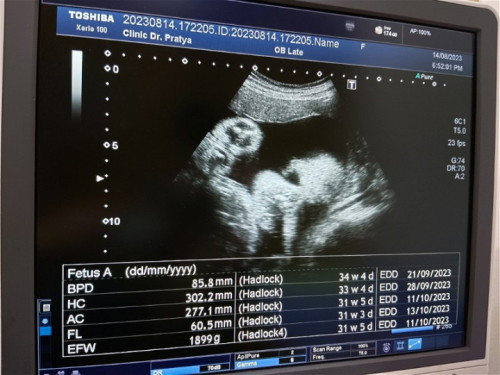

รอบศีรษะใหญ่ก่วาเกณ

ทองได้31Weekแล้ว หมอบอกรอบศีรษะลูกใหญ่ก่วาเกณ แต่ทุกอย่างปกติหมด มีแม่ๆบ้านไหนเป็นบ้างคะ แม่บ้านนี้รู้สึกไม่สบายใจ กลัวลูกเกิดมาไม่เเข็งแรง แต่ก่อนหน้านี้หมอก็บอกปกติตลอด

ถ้าหมอบอก ปกติ ก้อปกติคะ อายุครรภ์ขนาดจากการซาวมันคาดเคลื่อนได้ตลอดคะ